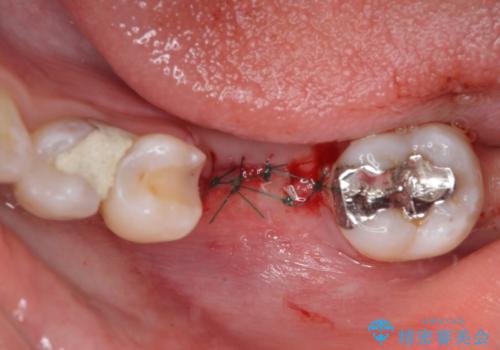

- ブリッジの歯のないところにインプラントを入れて、銀歯を白くやり替えたいと来院された患者様です。

歯の欠損している箇所にはインプラント治療をし、銀歯と仮詰めの部分はセラミックインレーにて補綴することとしました。

すべての治療の前に親知らずの抜歯も行っています。

- 外科手術のため、術後に痛みや腫れ、違和感を伴います

- 外科手術のため、術後に出血、痛みや腫れ、違和感を伴います